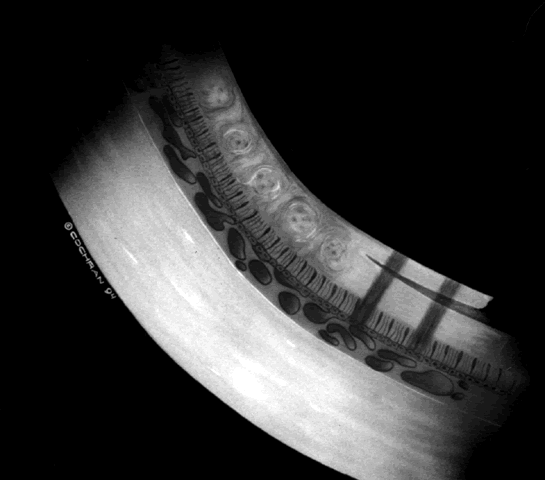

ROP accounts for a large number of retinal detachments in the pediatric population. The International Classification of Retinopathy of Prematurity helped greatly to improve communication about, and consequently treatment of, ROP. It describes affected eyes in terms of stage, zone, and absence or presence of plus disease18 (Figs. 1, 2, and 3). Screening of premature infants is an important feature in the care of ROP, which is perhaps the most significant and enduring finding of the Cryotherapy for Retinopathy of Prematurity Study (Cryo-ROP Study).19

Fig. 3. Dilated and tortuous vessels in the posterior pole, which by definition is plus disease.